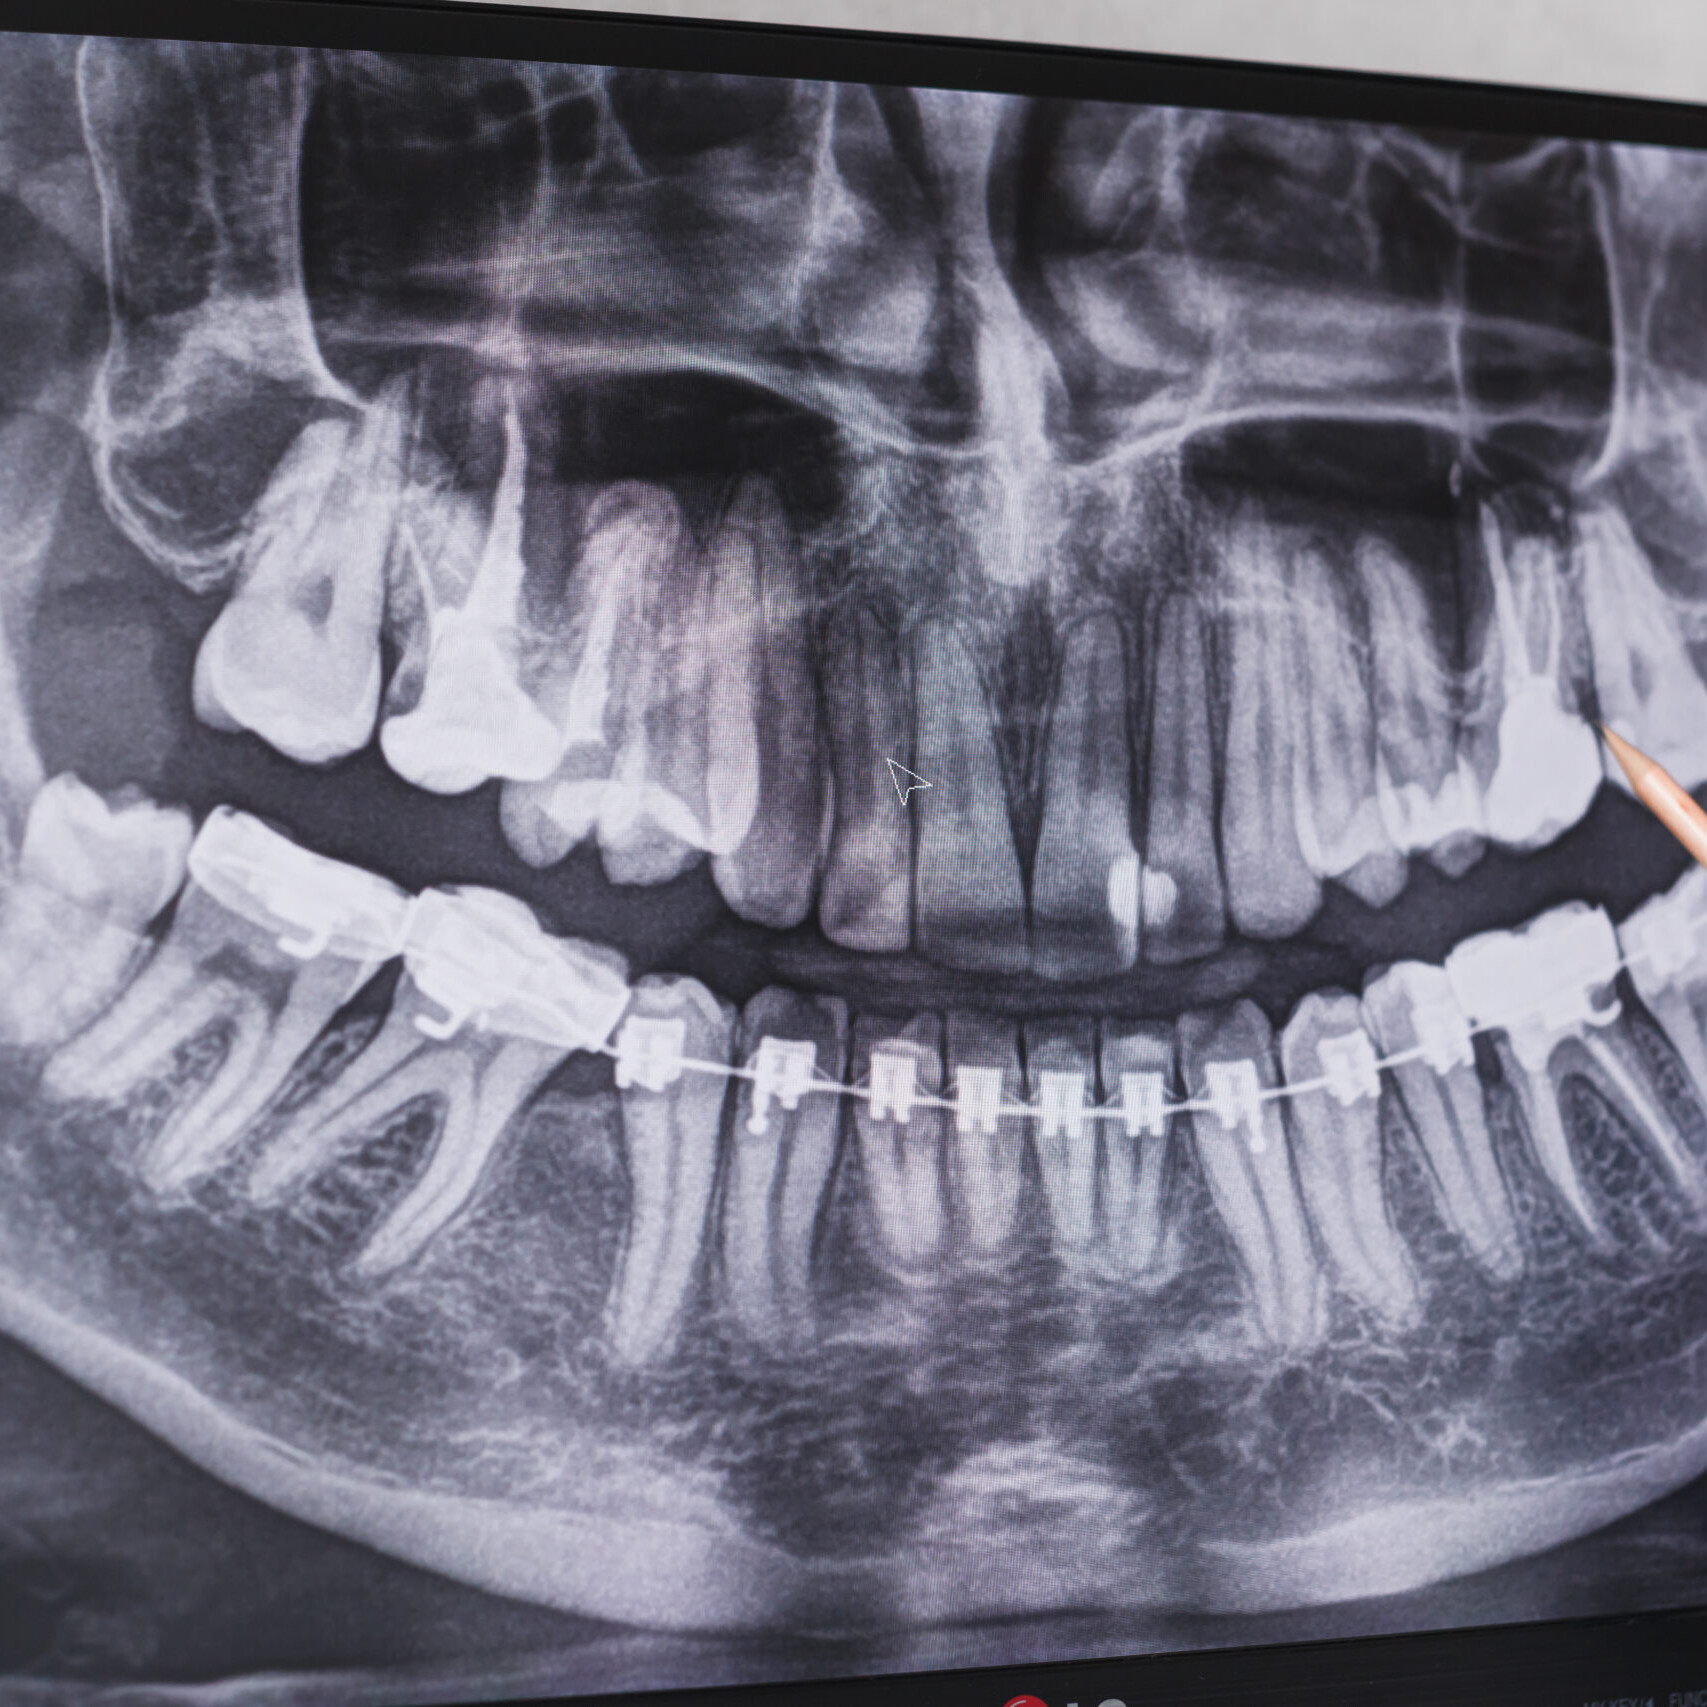

Nel nostro studio la diagnosi completa della bocca del paziente viene fatta utilizzando strumenti di ultima generazione come: Cone-Beam Tac, impronta ottica digitale, imaginig di radiologia 2D e 3D e sistema ottico Goccles.

La diagnostica comprende un’accurata anamnesi da parte dell’Odontoiatra dove vengono valutate le patologie del cavo orale, il parodonto (tessuto di sostegno del dente), le carie dentali, l’estetica del sorriso e la funzionalità dell’apparato masticatorio.

La radiologia 3D a differenza della prima consente di visualizzare le strutture dentali ed ossee in tutte le loro sezioni, permettendo un’indagine più approfondita quando ritenuta necessaria (ad esempio per la pianificazione implantologica).